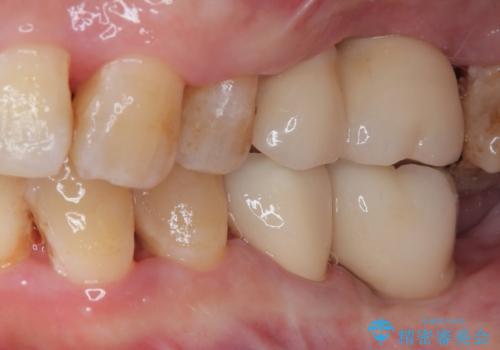

最終的に奥歯はオールセラミッククラウンによる補綴治療を行うこととしました。

インプラントにより咬合が回復したことで、治療開始時に認められた上顎前歯の動揺も改善されました。